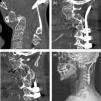

We demonstrate the case of a surgery in a patient with irreducible atlantoaxial dislocation (IrAAD) after C2 fracture. The challenges of this case were the flexed head in a forced position, impossibility of neck extension, and revision operation after posterior occipito-cervical fixation. The patient underwent the following surgeries: 1. A ventral release of C1-C2 using transcervical endoscopy; 2. Removal of occipito-cervical system and fibrous block resection in the posterior surfaces of the C1-C2; 3. Reducing of AAD and odontoid screw fixation; 4. Posterior C1-C2-C3 screw fixation. Ankylosing of C1-C2 and C2-C3-C4 fusion was verified by computed tomography scan. There was an improvement in patient status as observed by the increase of the SF-36 scale scores.